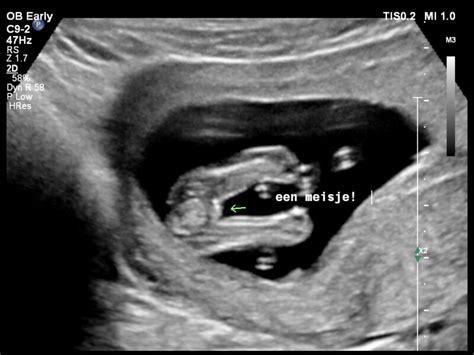

Echoscopie

Bij ons kunt u terecht voor echoscopie. Tijdens het eerste consult maken we een echo om de zwangerschap te bevestigen, dit vindt plaats tussen de 7e en de 9e week van de zwangerschap. Rond de 11e week vindt de termijnecho plaats, waarbij we de uitgerekende datum definitief vaststellen.